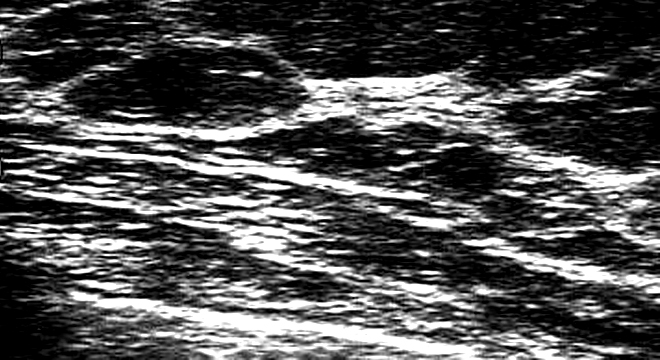

- Ekografia e gjinjve